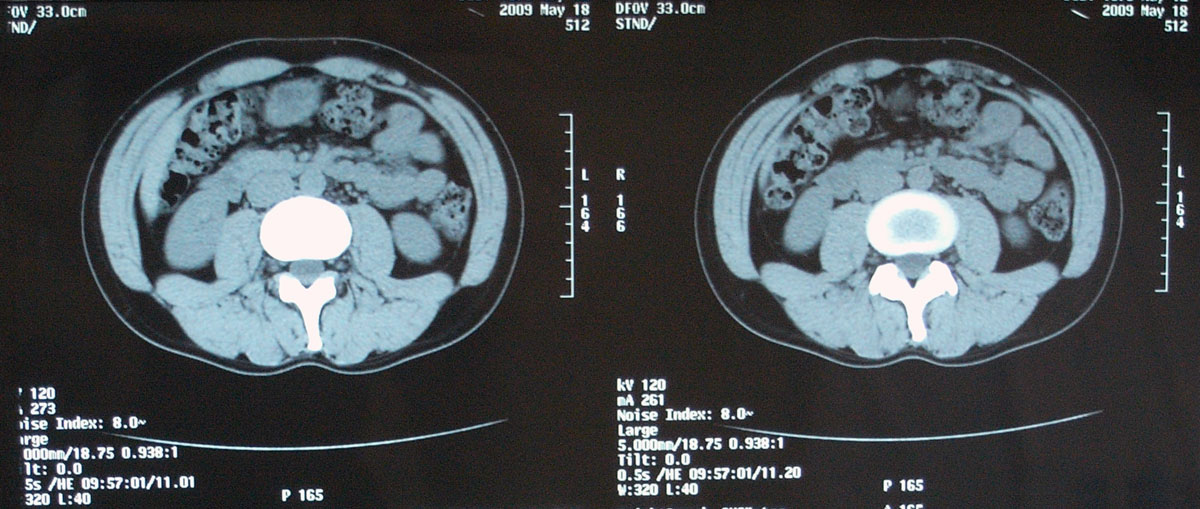

問題なし 【腫瘍マーカー】 HCGβ:<0.1 問題なし 【中性脂肪】 219→137 基準内(38-193)に入った 今回、検査画像をデータでもらってきた。 後腹膜の転移した箇所の前後4枚を2003年から2010年まで並べてみた。 http://gomatsushita.gozaru.jp/ct/album/index.html 2006/7/18の画像を見ると腫瘍がハッキリ見える。 BEP2クール後の9/27の画像では明らかに縮小もしくは消滅。

今回からCTの造影剤はありませんでした。

勘違いしてた・・・ なので単純CT。 横になって撮るだけなので非常に楽ですね。その分撮影される画像も解像度が低くなりますが・・・ しかし、思えば2005年末頃の単純CTからリンパ転移が疑われ始め、その次からはずっと造影剤を使用したCTだったわけだ。 2008年末の今、やっとそこへ戻ってきたという感じがした。 検査後の帰り、病院の最寄り駅のパン屋で朝食。 改札横に店があるのでガラス越しに行き交う多くの人を眺めながら思う。 2006年の入院中、ヨメも色々思いながらここを通ったんだろう、と。 何ヶ月も。 暑い日も雨の日も。 ただただ「感謝」あるのみです。 本日の検査結果は12/8。